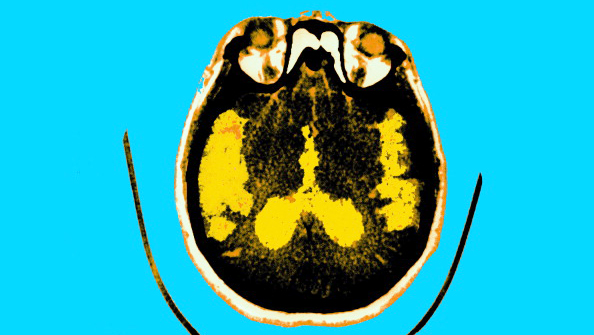

But don’t freak out about your pet just yet — it could be worse, and by worse I mean having a tapeworm eat your brain. There have been at least 2,000 cases of neurocysticercosis in the U.S. and 5 million or more cases worldwide, which cause epileptic-like symptoms when this normally gut-eating parasite takes up residence in the cerebrum. There’s also Chagas disease, most commonly found in Latin America, which affects the cardiovascular system and can lead to heart failure. In 2007, U.S. blood banks began screening for the disease and found alarmingly high rates among poor communities in Florida and Texas.

Not only are parasites a public health concern, but also they take an untold toll on human intelligence. Researchers at Johns Hopkins found ACTV-1, a chlorovirus, in two out of every five subjects. Normally found in algae, the pathogen somehow made a rapid evolutionary leap from infecting plant matter to humans and the cost was diminished cognition in those participants who were infected. According to The American Scholar, “When compared with those who did not harbor the virus, those infected were about 10 percent slower to make calculations and had a reduced attention span, suggesting that the virus compromised their ability to calculate, to focus, and to process visual information — disadvantages in the classroom, on the job, and in other familiar learning situations.”